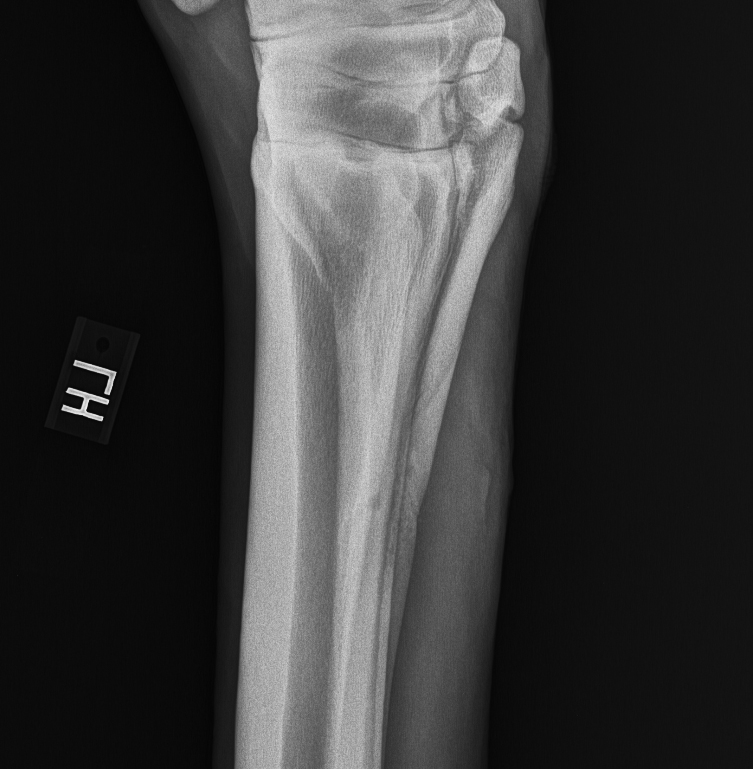

The splint bones, found in both the front and back limbs, are small, narrow bones found on allowed the proper amount of stall rest, lameness resulting from splint bone fractures is likely to recede. The splint bone distal to the fracture was removed in nine horses in which the attachment of the splint bone to the cannon bone via the interosseous ligament did not provide adequate stability. Closed fracture (including stress fracture).

As we noted before, the fracture may be displaced or undisplaced. A bone fracture, also known as frx or fx is a clinical condition characterized by the loss of overview of bone fracture. A healthcare provider can usually treat a broken bone with a cast or splint. Many can be treated successfully with rest alone. Causes of bone fractures include trauma, overuse, and diseases that weaken bones. A broken bone or bone fracture occurs when a force exerted against a bone is stronger than the bone can bear. Most fractures result from force applied to a bone. Splinting a suspected fracture or dislocation can help prevent further injury and assist with pain proper techniques for splinting upper extremities and lower extremities is an important tool in case of. Why should fractured bone be splinted? A study by sherlock and archer in 2008, found that splint bone fractures were the most. A fracture in which the bone fragments are still partially joined. Fractures of the splint bones can occur as a result of external trauma, such as a kick from another horse or from the horse interfering with itself. The splint bone distal to the fracture was removed in nine horses in which the attachment of the splint bone to the cannon bone via the interosseous ligament did not provide adequate stability. The splint bones, found in both the front and back limbs, are small, narrow bones found on allowed the proper amount of stall rest, lameness resulting from splint bone fractures is likely to recede. Splint bone fracture results in 2 or more fragments. The fractured bone has broken the skin. Fractures (and other musculoskeletal injuries) vary greatly in severity and in the treatment needed.